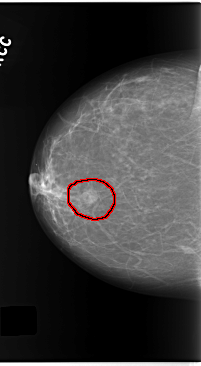

C_0140_1.RIGHT_CC

FILE: C_0140_1.RIGHT_CC.OVERLAY

TOTAL_ABNORMALITIES 1

ABNORMALITY 1

LESION_TYPE MASS SHAPE ROUND MARGINS MICROLOBULATED

ASSESSMENT 4

SUBTLETY 5

PATHOLOGY MALIGNANT

TOTAL_OUTLINES 1

BOUNDARY